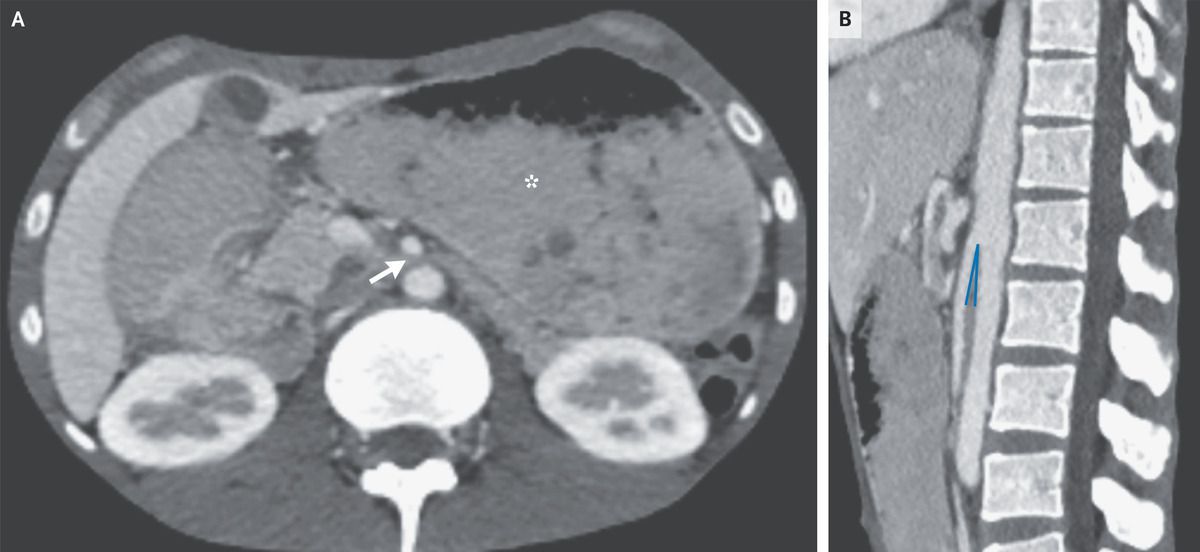

A 26-year-old man from Somalia presented to the emergency department with a 5-month history of dry cough, night sweats, and unintentional weight loss of 18 kg. During this period, epigastric pain and episodes of postprandial vomiting had also developed. His body-mass index (the weight in kilograms divided by the square of the height in meters) was 11. Physical examination was notable for cachexia and abdominal distention with diffuse, mild tenderness to palpation. On the basis of chest imaging and sputum studies, a diagnosis of pulmonary tuberculosis was made. Intravenous antituberculous treatment was initiated, but the patient continued to have postprandial vomiting. Subsequent contrast-enhanced computed tomography of the abdomen showed a paucity of mesenteric and subcutaneous fat, dilatation of the stomach (Panel A, asterisk), and compression of the duodenum between the superior mesenteric artery and the aorta, with an aortomesenteric distance of 3 mm (reference range, 10 to 20) (Panel A, arrow) and an aortomesenteric angle of 7 degrees (reference range, 45 to 60) (Panel B). A diagnosis of superior mesenteric artery syndrome due to cachexia from tuberculosis was made. A nasogastric tube was inserted and parenteral nutrition was initiated; however, the patient opted to leave the hospital after 2 weeks and was lost to follow-up.